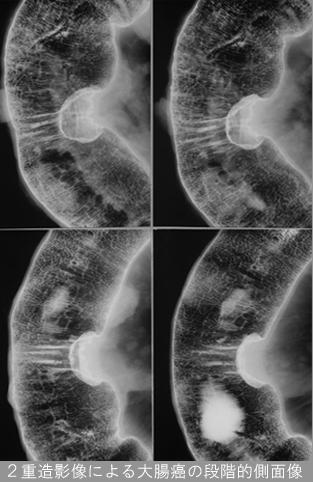

[Image-ID:12154]